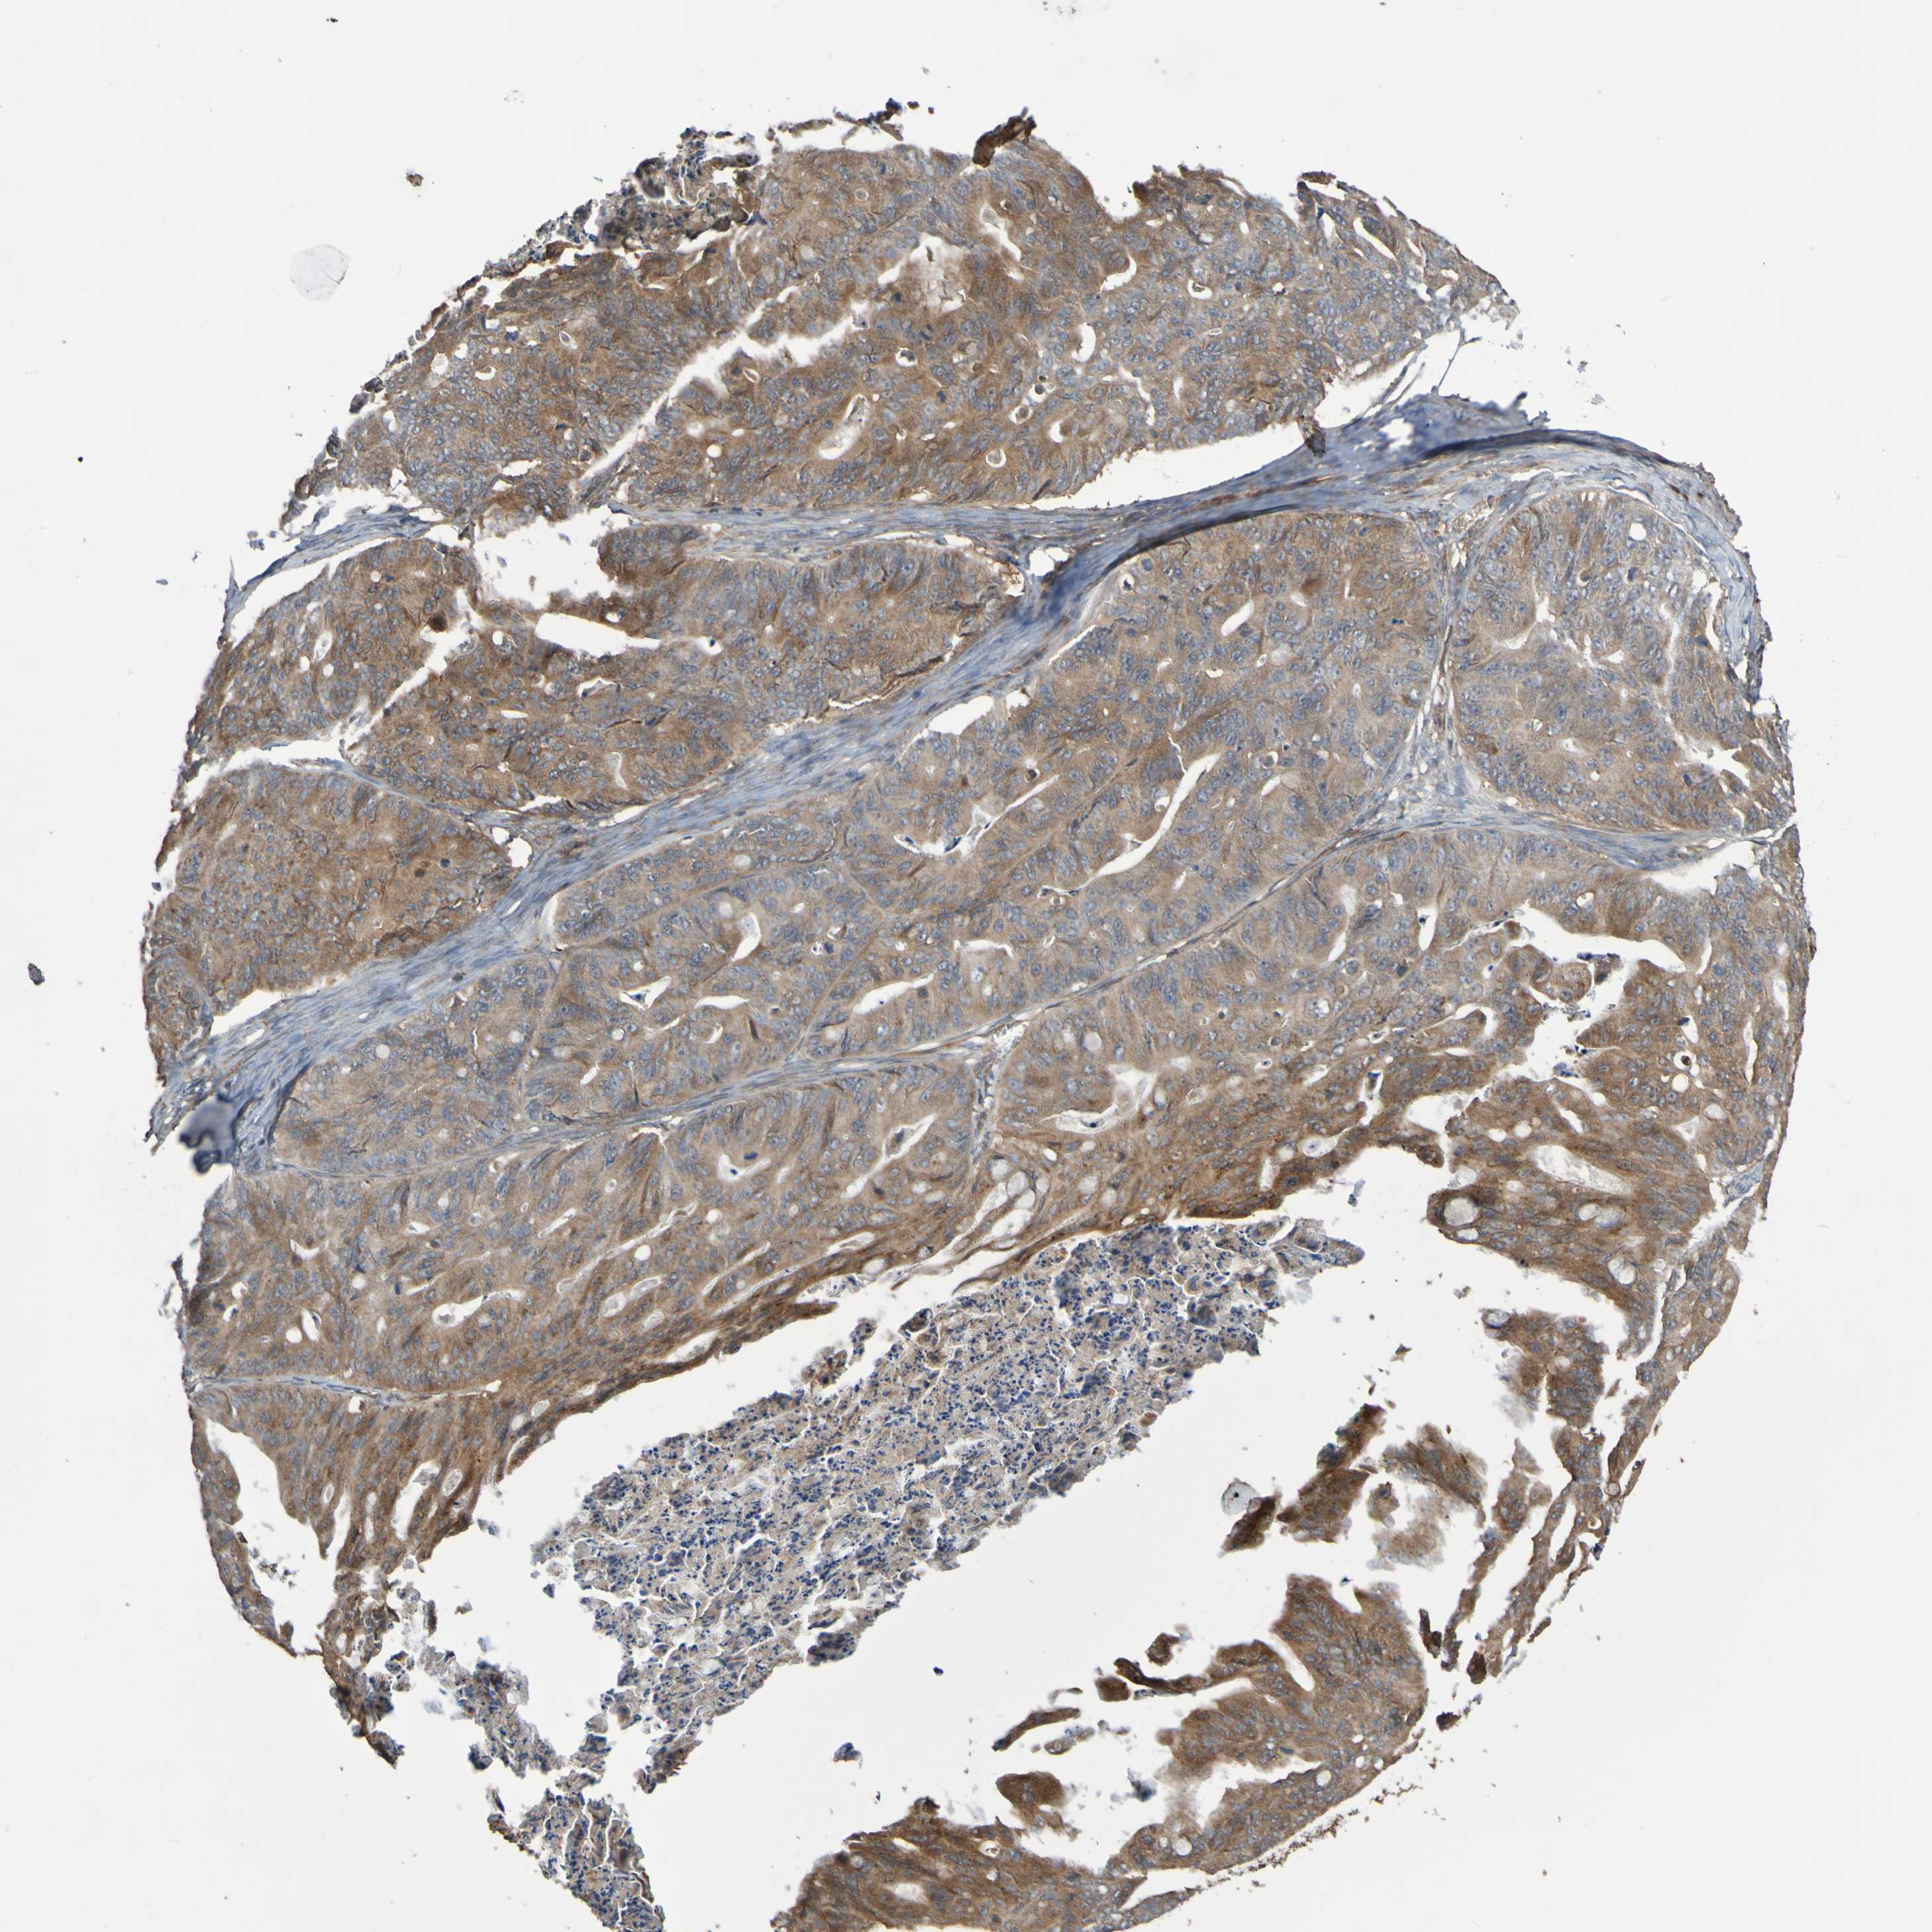

OVARIAN CANCER - Protein expressioni

A mouse-over function shows sample information and annotation data. Click on an image to view it in a full screen mode. Samples can be filtered based on level of antibody staining by selecting one or several of the following categories: high, medium, low and not detected. The assay and annotation is described here.

Note that samples used for immunohistochemistry by the Human Protein Atlas do not correspond to samples in the TCGA dataset.

Antibody stainingi

Antibody staining in the annotated cell types in the current human tissue is reported as not detected, low, medium, or high, based on conventional immunohistochemistry profiling in selected tissues. This score is based on the combination of the staining intensity and fraction of stained cells.

Each image is clickable and will lead to virtual microscopy that enables deeper exploration of all samples and also displays staining intensity scores, fraction scores and subcellular localization as well as patient and tissue information for each sample.

Antibody CAB010911

Staining

High

Medium

Low

Not detected

Intensity

Strong

Moderate

Weak

Negative

Quantity

>75%

75%-25%

<25%

None

Location

Nuclear

Cytoplasmic/membranous

Cytoplasmic/membranous,nuclear

Cystadenocarcinoma, serous, NOS

Carcinoma, endometroid

Cystadenocarcinoma, mucinous, NOS

Carcinoma, NOS